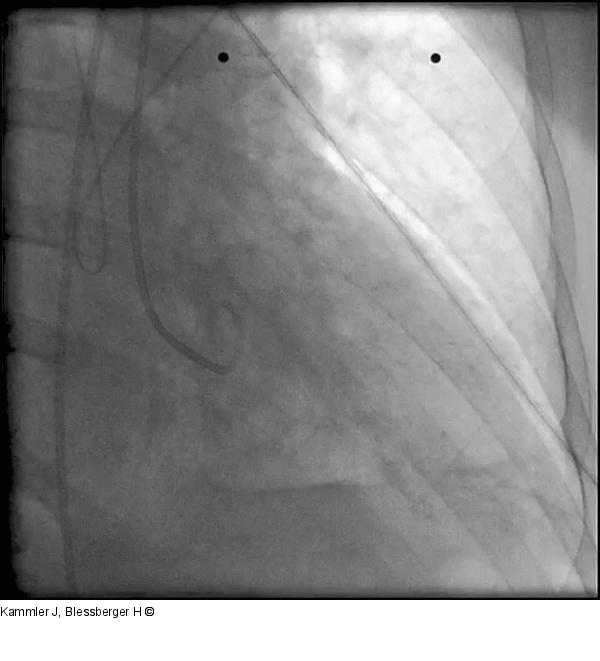

Abbildung 9: Film 5